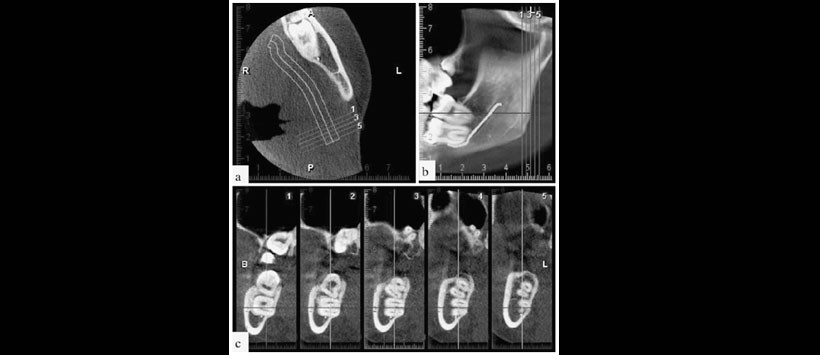

Figura 3: La tomografía computarizada de haz cónico (TCHC) que muestra la proximidad de la pieza 4.7 con el conducto dentario inferior. A (vista axial), B (vista sagital y C (vista transaxial).